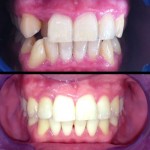

Este é um caso mais simples de se fazer e com um valor (custo-benefício) bastante cómodo.São somente 4 implantes na arcada inferior suportando uma barra sobre a qual será transferido em parte o esforço mastigatório. É confeccionada em RESINA como uma prótese total convencional.